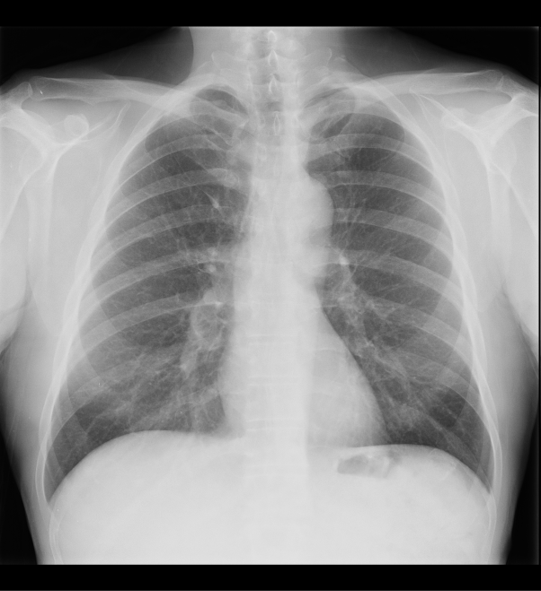

Rx PA de tórax